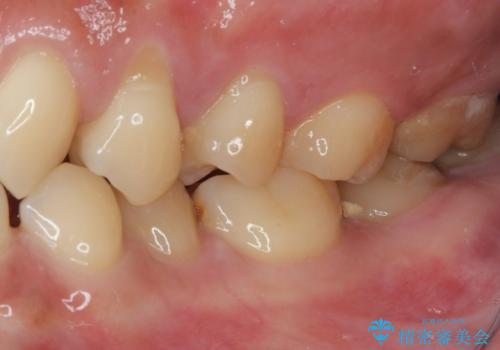

- 食いしばりと強いブラッシングにより、上顎小臼歯2本に知覚過敏を感じるようになったとのことで来院された患者様です。

歯肉退縮により歯根部が露出し、冷たい飲み物に痛みを感じる状態でした。

根面被覆を目的として歯肉移植術を行うこととしました。

歯肉が薄い状態であったため、歯肉退縮が起こりやすいと判断された患者様でした。

根面被覆を達成するとともに、歯肉の厚みを増すことで、今後歯肉退縮を起こしにくくするよう配慮した処置としました。